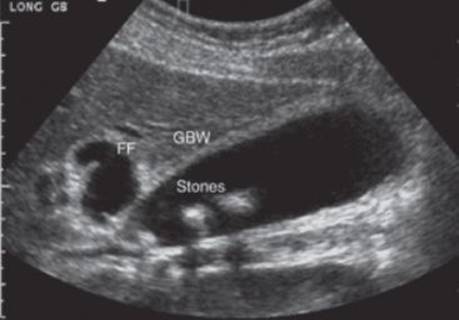

Laboratory evaluation including a complete blood count and liver function tests was obtained. The white blood cell count was mildly elevated at 13 × 103/μL. Liver and pancreatic enzymes were normal (total bilirubin 1.0 mg/dL, indirect bilirubin 0.5 mg/dL, alkaline phosphatase 90 U/L, lipase 35 U/L). A RUQ abdominal ultrasound was performed (Figure 2) and demonstrated a normal gallbladder wall with multiple hyperechoic shadowing consistent with gallstones. The common bile duct measured 0.7 cm.

FIGURE 2 • RUQ abdominal ultrasound revealing cholelithiasis.